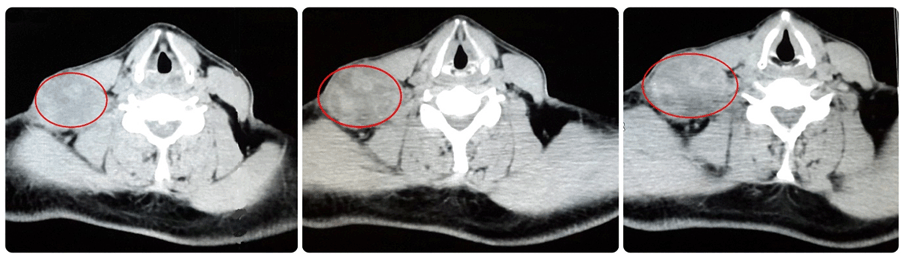

A 50-year-old male presented with history of hypertension and hemorrhagic stroke in 2012 with sequel of right hemiparesis. The patient presented with a right supraclavicular firm, incompressible and immobile swelling of 55 mm. Body computed tomography (CT) with contrast was done. It showed left renal mass in lower pole measuring 65x38 mm as a focal bulging of the renal contour, mainly isodense to the renal parenchyma. The corticomedullary phase clearly showed renal malignancy which was moderately and heterogeneously enhancing (Figure 1). Heterogeneous contrast enhancement on imaging should always suggest renal malignancy preoperatively. There was a secondary heterogeneous lesion in the right supraclavicular hollow measuring 56x42 mm with central necrosis (Figure 2). Fine needle aspiration (FNA) of right supraclavicular tumor showed metastasis of well differentiated adenocarcinoma. His biopsy was unsatisfactory. He was evaluated by urology and oncology services so it was decided to like radiotherapy for local control and subsequen treatment with interferon α 5 million IU/week and sunitinib 50 mg/day for one year for down staging (six weeks cycles). Treatment was started with pazopanib 800 mg/day. The lesion increased in size for six months. He had poor clinical response. He was evaluated by head and neck surgeons and surgery was done: resection of cervical tumor of level V and right cervical lymphadenectomy of levels II, III, IV, V (Figure 3). The surgery was done on third day of hospitalization. Ambulatory monitoring was done by head and neck and oncology services. Microscopic study of respected lymph nodes revealed clear cell renal carcinoma (ccRc). After 45 days, laparoscopic nephrectomy was performed. The immunohistochemical profile was the same for both the neck and renal tumor. No recurrences occurred after two years of follow-up.

Figure 2: Lesion heterogeneous in the right supraclavicular hollow of 56 x 42. Secondary lesion heterogeneous with central necrosis